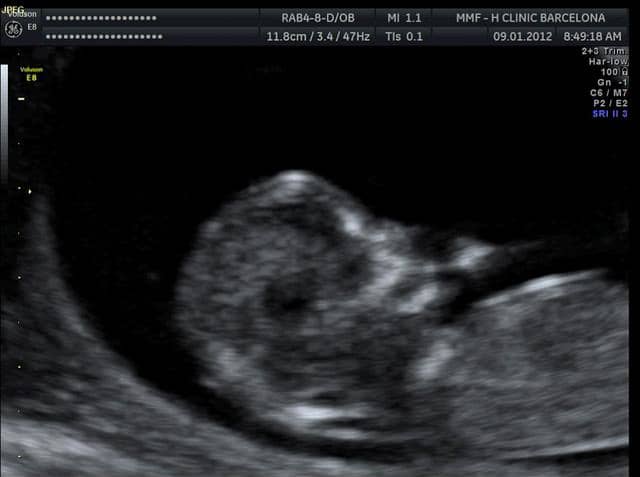

Cambios en tu cuerpo a las 11 semanas de embarazo. Es posible que tu respiración sea más rápida y que transpires más de lo usual. Durante a 11ª semana de gestação o seu bebê já mede cerca de 5 cm e a cabecinha tem quase a metade do comprimento do corpo.

Minúsculos botões dentários começam a aparecer sob as gengivas do bebê. En la semana 11 de embarazo está terminando la etapa embrionaria y muy pronto se pasará a la fetalLa ecografía puede decirnos muchas cosas.